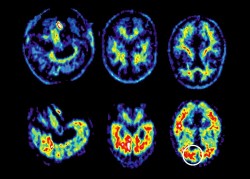

| Các nhà nghiên cứu vừa xác định được một đầu mối mới, cho phép chẩn đoán chính xác hơn ở những bệnh nhân mắc các triệu chứng Alzheimer. (Nguồn: Nature) |

Trong bệnh Alzheimer, một loại protein, gọi là "tau", đóng vai trò trung tâm trong việc khởi phát các triệu chứng, bằng cách tích tụ trong các tế bào thần kinh dưới dạng tập hợp, lan đến toàn não bộ. Nhưng cho đến nay, căn bệnh này chỉ có thể được xác nhận sau khi khám nghiệm tử thi.

Theo một nghiên cứu được công bố trên tạp chí Nature Communications, các nhà nghiên cứu của UCL vừa xác định được một đầu mối mới, cho phép chẩn đoán chính xác hơn ở những bệnh nhân mắc các triệu chứng này.

Bởi hiện tại, bệnh đang phát triển ở những vùng não bất thường, điều này làm sai lệch chẩn đoán và do đó không cho phép áp dụng phương pháp điều trị thích hợp.

Nhóm các nhà khoa học từ Viện Khoa học Thần kinh và Viện Duve tại UCL do Giáo sư Bernard Hanseeuw dẫn đầu đã so sánh protein "tau" tổng hợp và cùng loại protein hòa tan vì ở dạng này, protein có ưu điểm là có thể được đặc trưng hóa trong suốt cuộc đời của bệnh nhân và điều này chẩn đoán bằng cách chọc tủy sống.

Nghiên cứu này có thể thực hiện được nhờ một công cụ mạnh mẽ hiện có tại Viện Duve của UCL, phép đo phổ khối, có khả năng mô tả đặc tính của protein. Nghiên cứu xác nhận rằng vấn đề về bệnh thoái hóa thần kinh là do việc loại bỏ hoặc biến đổi các protein sau khi chúng được sản xuất. Điều này mở ra con đường phát triển một dấu ấn sinh học, từ đó chẩn đoán, nhưng cũng để xác định những sửa đổi nào khiến protein này tổng hợp.

Khám phá trên mở ra con đường trị liệu mới cho bệnh nhân Alzheimer.